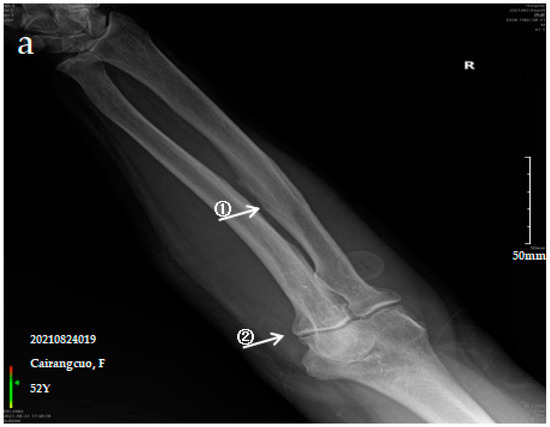

The patient is a 52-year-old female with persistent pain in the limbs and joints at rest who can engage in normal physical labour. The anteroposterior actinogram of the upper limb (Figure 1a) shows ossification of the interosseous membrane of the radius and ulna, with a cotton wadding appearance. Periarticular tendon and pronator teres muscle ossification, and degenerative changes in the elbow joint can be seen. The anteroposterior actinogram of both lower limbs (Figure 1b) shows ossification of the tibiofibular interosseous membrane, the shadow of the colliculus bony protrusion at the tibial and fibular and ossification of the knee joint capsule and tibial collateral ligament.

Figure 1.

X-ray imaging of SF patients. The anteroposterior actinogram of the upper limb (a) and both lower limbs (b) of patient with mild SF, the anteroposterior actinogram of the upper limb (c) and both lower limbs (d) of patient with moderate SF, the anteroposterior actinogram of the upper limb (e) and both lower limbs (f) of patient with severe SF. ①: ossification of interosseous membrane; ②: degeneration of the elbow joint; ③: Ossification shadow; ④: Ossification of knee joint capsule; ⑤: ossification of soleus tendon.